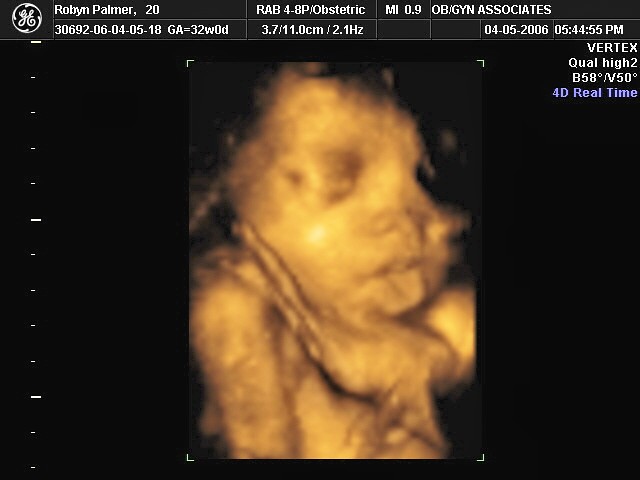

Los ultrasonidos 4D son una evolución de los tradicionales ultrasonidos 2D. Mientras que los ultrasonidos 2D producen imágenes en blanco y negro y planas, los ultrasonidos 4D producen imágenes en tiempo real en 3D y con movimiento. Esto permite ver al bebé en desarrollo de una forma mucho más realista y detallada.

Carsons 3d Ultrasound - Debi Stith - FlickrDesde una perspectiva emocional, los ultrasonidos 4D son importantes porque permiten a las madres sentir una conexión más fuerte con su bebé en desarrollo. Ver a su hijo en movimiento y en 3D puede ser una experiencia emocionante e inolvidable. Además, estos ultrasonidos también pueden ser una forma única de compartir la emoción del embarazo con familiares y amigos.